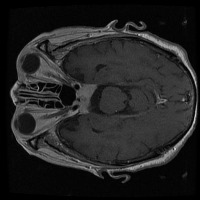

tumor otak Computer Vision Project

Medical Diagnostics: This model can be used for assisting healthcare professionals in diagnosing brain tumors by classifying them into glioma, pituitary, or meningioma, which can save time and lead to early and accurate disease diagnosis.

Training medical students and resident doctors: The model can be used as a training tool for medical students and resident doctors to better understand and identify different types of brain tumors from MRI images.